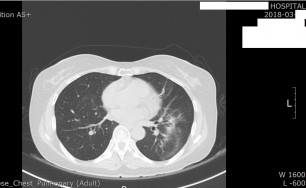

숨케어한의원에서는 전화예약을 받고 있습니다. 내원시 엑스레이, CT사진, 폐기능검사지를 가지고 오시면 자세한 상담이 가능합니다.